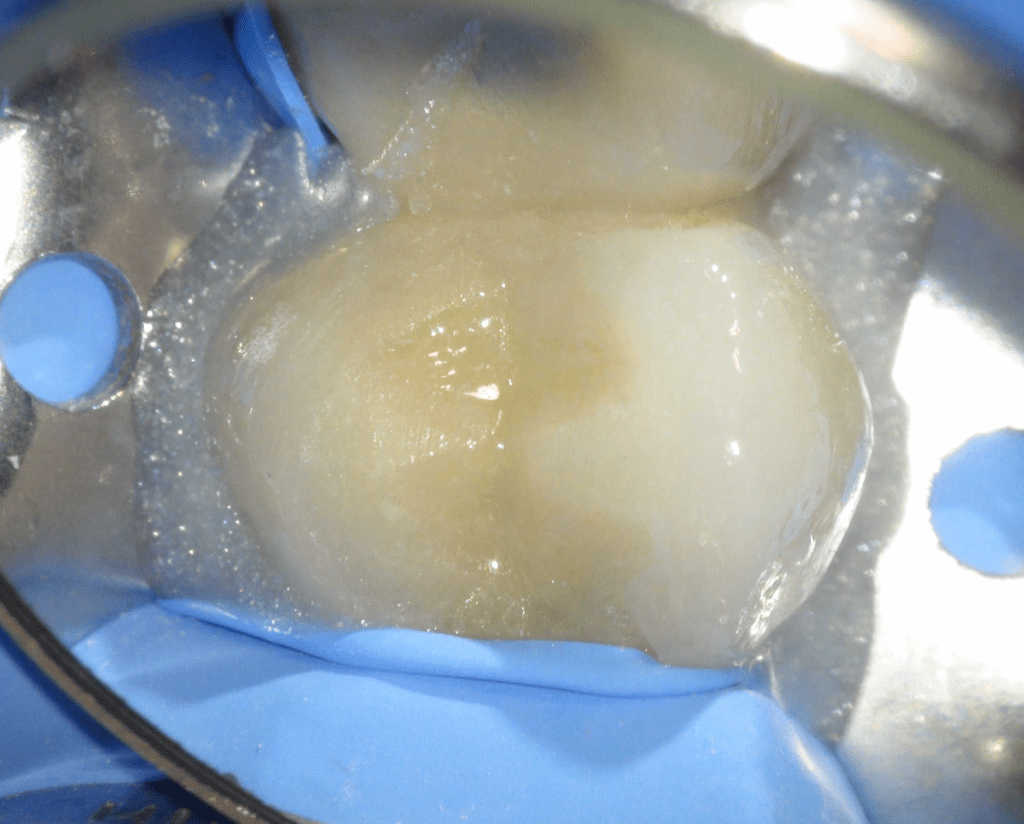

Fisura, remoción amalgama para explorar